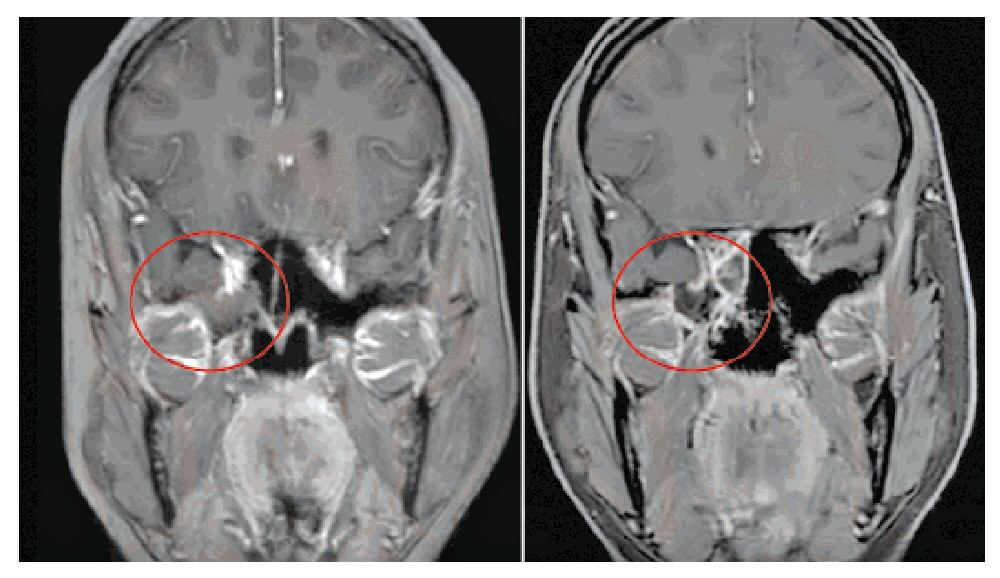

邓泽义主任团队术前通过高分辨率CT、脑脊液生化、头颅MR+MRV等精准定位漏口,明确缺损范围及与周边结构关系,排除血管畸形。手术无需开颅,采用经鼻内镜微创入路,借助鼻腔自然通道直达颅底缺损,清理疝出组织,取自体脂肪、筋膜多层加固修补,全程避开重要血管神经。术后复查MR显示修复良好,罗女士“清鼻涕”消失,不适症状完全缓解,已康复出院。